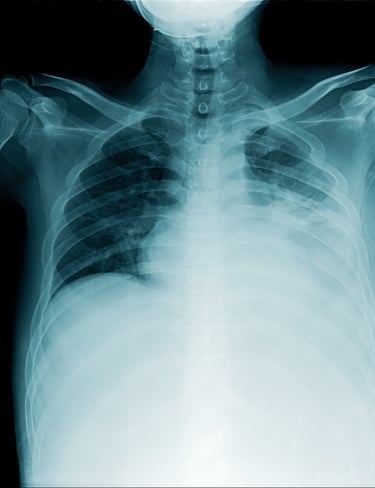

Tuberculosis

Tuberculosis (TB) remains one of the world’s deadliest infectious diseases, killing nearly two-thirds of untreated patients within three years. While curable with proper treatment, delays or incomplete care allow the disease to progress, leading to severe illness, drug resistance, and death.